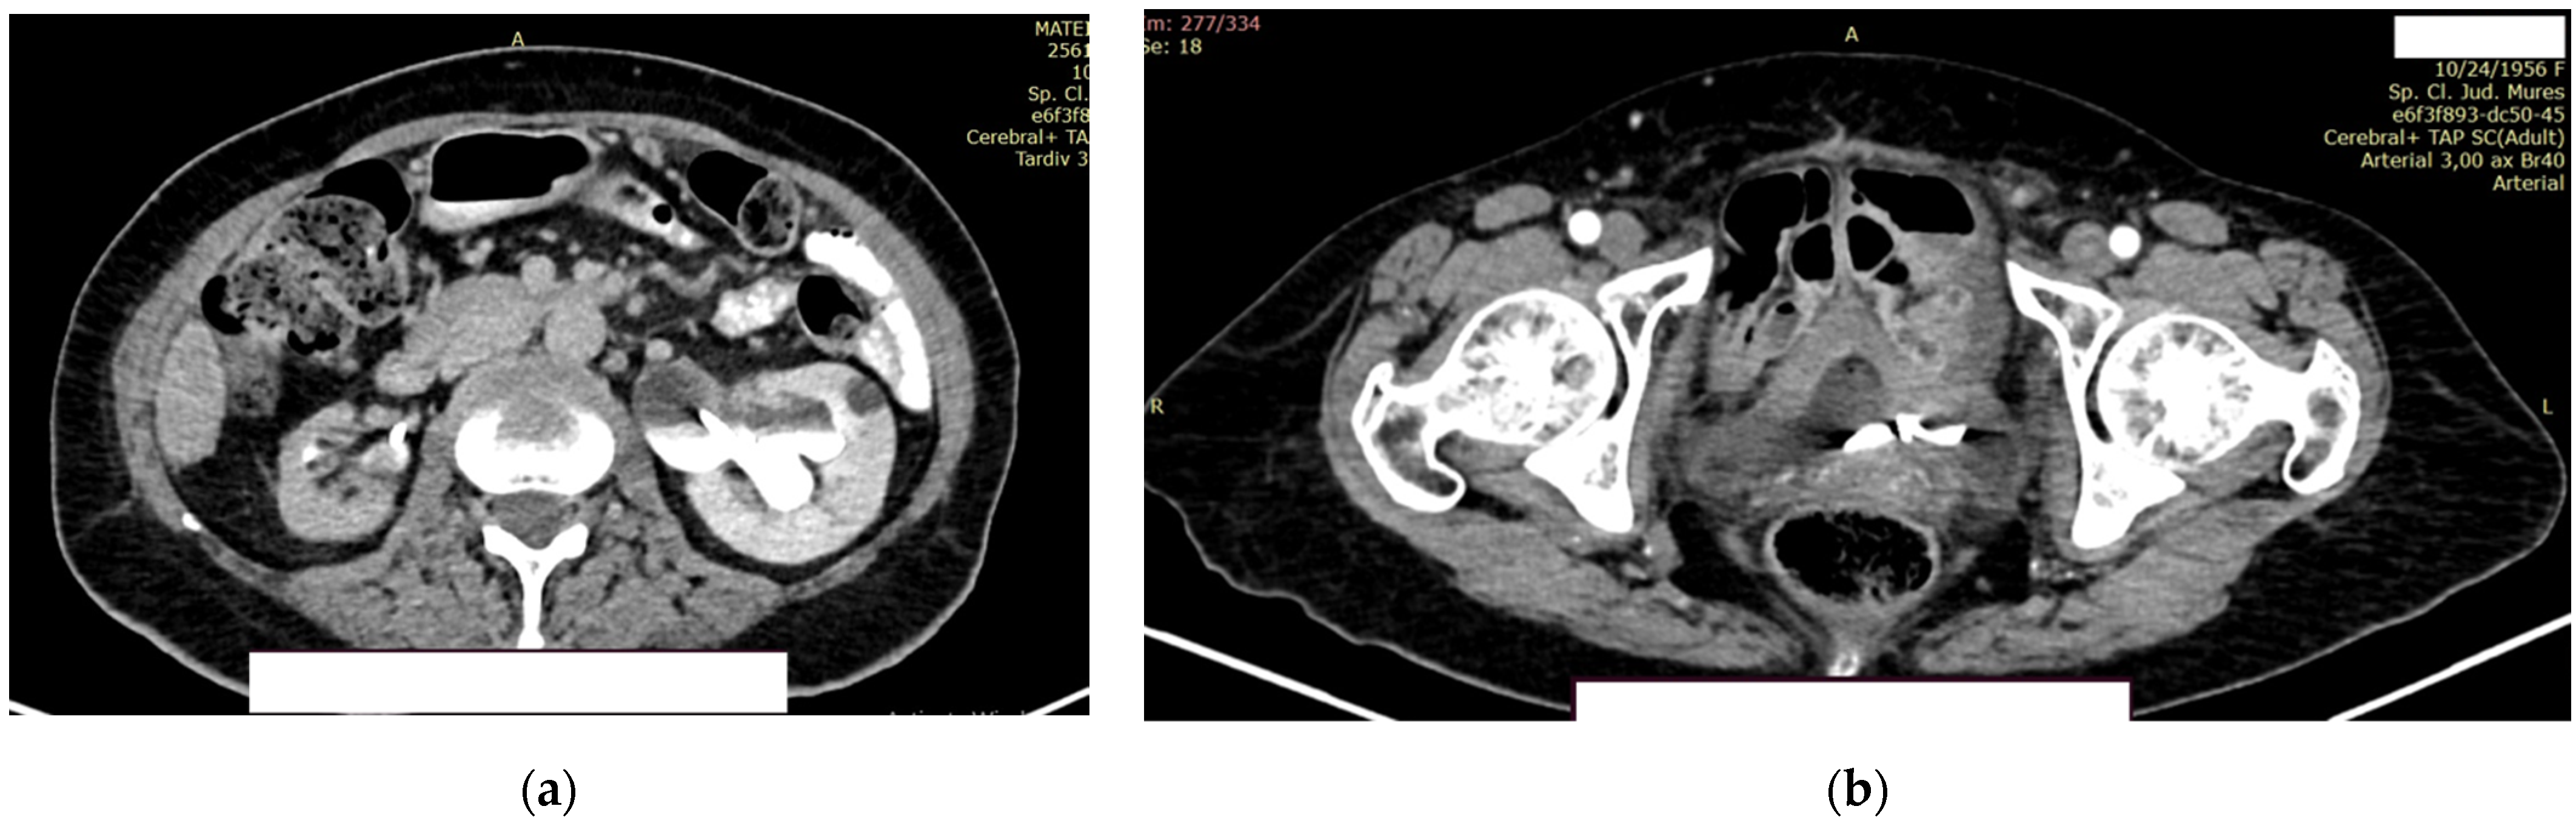

The right kidney is hypotrophic, with the presence of ureteral stent, without stones, and without stasis and presence of secretion. The left kidney showed a normal position of the stent, II/III grade hydronephrosis, secretion, and excretion. A retroperitoneal lymph node, measuring up to 10 mm, was observed, with some calcification (Figure 9a).

Figure 9.

Contrast CT aspect. (a) The right kidney is hypotrophic, with a ureteral stent in place, no stasis, and secretion present. The left kidney also has a ureteral stent, with grade II/III hydronephrosis, and both secretion and excretion are present. (b) The walls of the urinary bladder are concentrically thickened. It is unclear whether the distal intravesical portion of the ureter has any tumor formation.

In the urinary bladder, concentrically thickened walls are described. It cannot be assessed if the distal, intravesical portion of the ureter presents tumors formation (Figure 9b).